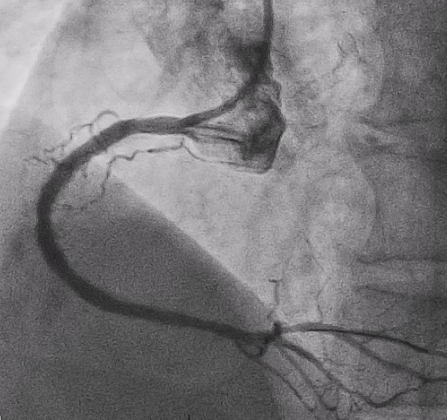

Subsequent coronary angiography identified a pseudoaneurysm in the right coronary artery (RCA), without any evidence of extravasation.

In this coronary catheterization procedure, a guidewire was used to cross the lesion and advanced to the posterolateral branch (PL). An intravascular ultrasound (IVUS) examination was conducted, revealing a pseudoaneurysm in the mid-right coronary artery (m-RCA). To cover the pseudoaneurysm, a 3.5 x 16 mm cover stent was deployed in the m-RCA at a pressure of 16-18 atmospheres for 15-20 seconds, repeated twice. Subsequently, the cover stent was further post-dilated with a 3.75 x 15 mm non-compliance balloon at 18-20 atmospheres for 10 seconds, also performed twice. Optical coherence tomography (OCT) was then performed, showing a post-dilation stent MSA of 7.40 mm² with good apposition and expansion. The cover stent was additionally dilated with a 4.0 x 30 mm drug-eluting balloon (DEB) at 6 atmospheres for 60 seconds. The final angiography demonstrated TIMI grade 3 flow without any extravasation.

Case Summary

Post-intervention angiography demonstrated improved blood flow in the affected artery. The RCA pseudoaneurysm was effectively sealed, and subsequent imaging confirmed appropriate stent placement. The use of IVUS and OCT allowed for optimal sizing and placement, leading to a successful outcome.